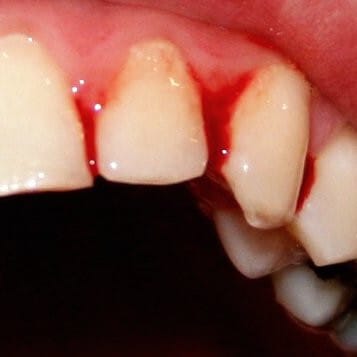

🟥 출혈 위치

피부, 점막 (코피, 잇몸 출혈, 멍, 월경 과다 등)

➡ 혈소판은 표면 출혈 부위에서 먼저 작용합니다. 혈소판 수가 부족해지면 손상된 혈관벽을 복구하지 못해 얕은 출혈이 잘 생깁니다.

🟥 출혈 양상

점상출혈, 자반, 바늘자국 출혈 등 작고 넓게 퍼지는 형태

➡ 모세혈관이나 세정맥 출혈을 제어하지 못해 미세한 출혈이 많습니다.